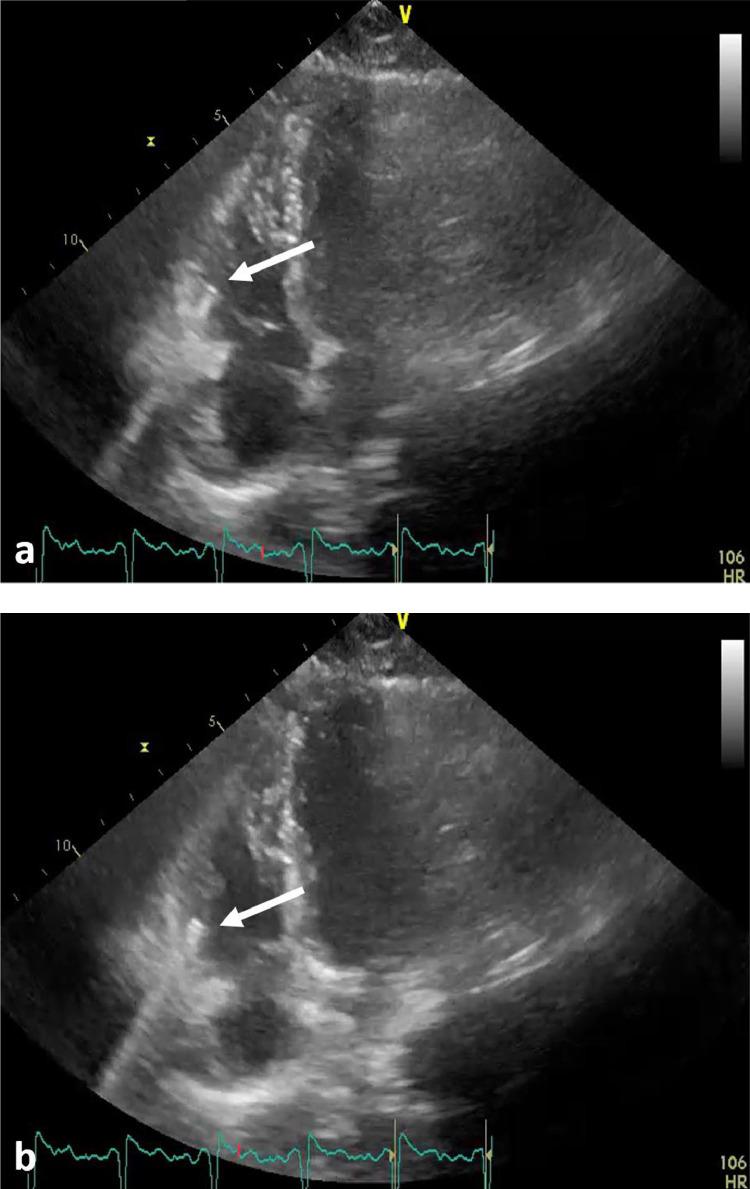

Pellet embolism to the heart following gunshot injuries is an unusual event that requires a fast diagnosis. Imaging assessment is necessary to locate the projectiles and look for associated injuries. We present a case of a 41-year-old woman admitted after sustaining 2 gunshot wounds in the abdomen and left thigh, with the initial computed tomography (CT) scan showing a metallic object next to the right ventricle. Further radiological evaluation included transthoracic echocardiography and electrocardiogram-gated cardiac CT scan which confirmed the diagnosis of a migrating pellet to the right ventricle, entrapped within the trabeculations. Electrocardiogram-gated cardiac CT has a major role in detailed evaluation of bullet embolism to the heart cavities and guides the management.

枪伤后心脏出现弹丸栓塞是一种罕见事件,需要快速诊断。进行影像学评估对于定位投射物并查找相关损伤很有必要。我们报告一例41岁女性,其腹部和左大腿遭受两处枪伤后入院,初始计算机断层扫描(CT)显示右心室旁有一金属物体。进一步的放射学评估包括经胸超声心动图和心电图门控心脏CT扫描,这些检查确诊了一枚弹丸迁移至右心室并被困于小梁内。心电图门控心脏CT在详细评估心脏腔室的子弹栓塞中起主要作用,并指导治疗。